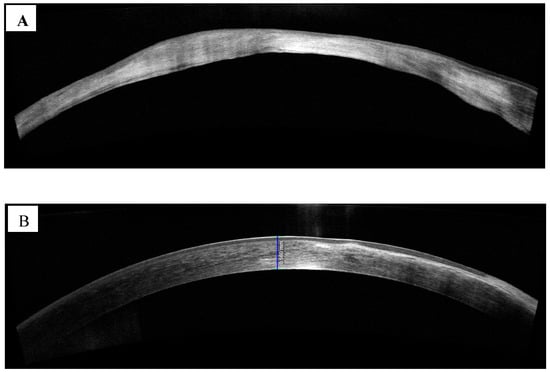

- Soliman, W.; Fathalla, A.M.; El-Sebaity, D.M.; Al-Hussaini, A.K. Spectral domain anterior segment optical coherence tomography in microbial keratitis. Graefe’s Arch. Clin. Exp. Ophthalmol. 2013, 251, 549–553. [Google Scholar] [CrossRef]

- Oliveira, M.A.; Rosa, A.; Soares, M.; Gil, J.; Costa, E.; Quadrado, M.J.; Murta, J. Anterior segment optical coherence tomography in the early management of microbial keratitis: A cross-sectional study. Acta Med. Port. 2020, 33, 318–325. [Google Scholar] [CrossRef]